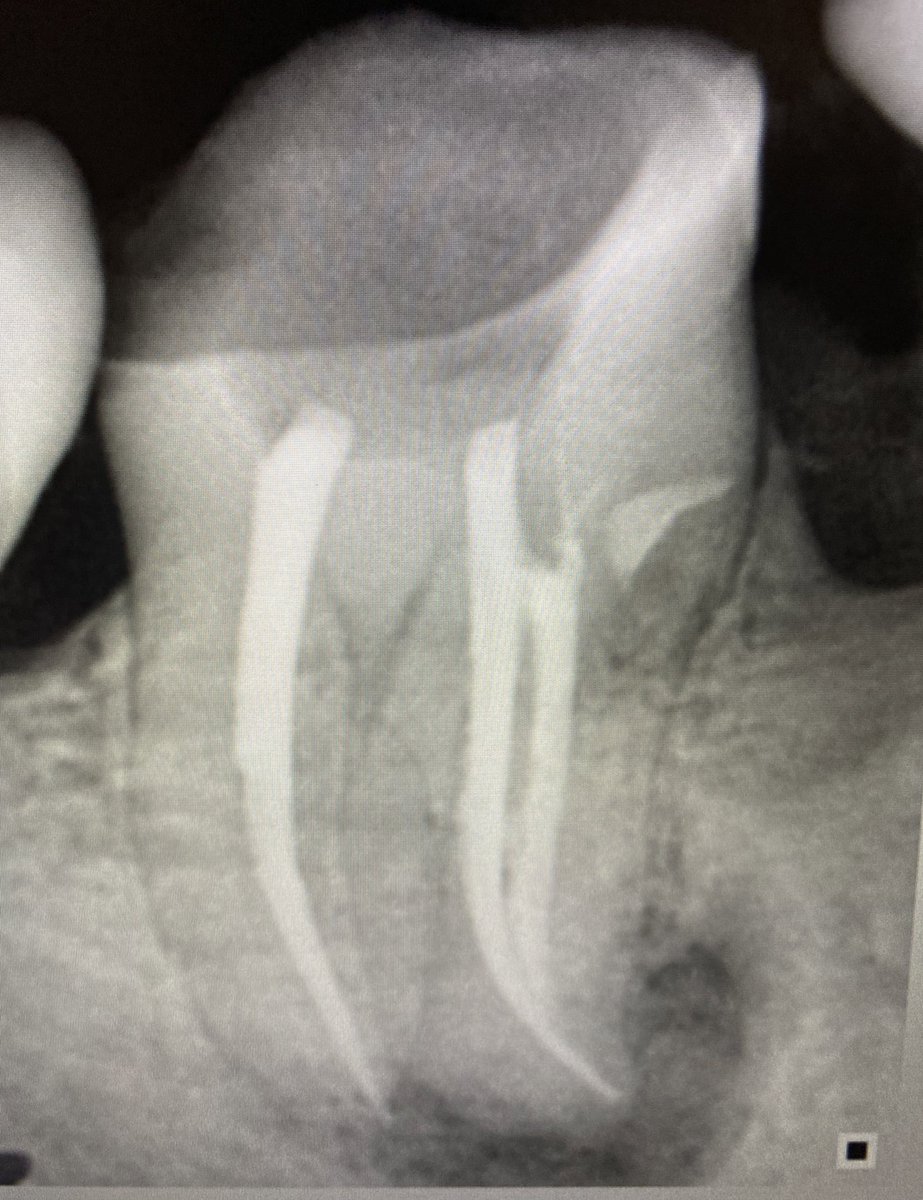

هنا يوجد. Large PA lesion

حضر المريض بضرسين مقرره للخلع من كذا عياده وابلغته انه طبعا بالامكان المحافظه عليه وتم ذلك في جلسه واحده